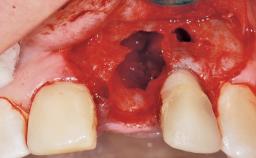

A 42-year-old female patient was referred to our clinic at the School of Dentistry of the University of São Paulo in November 2004, presenting a deficient restoration in the upper left central incisor. The clinical examination revealed no gingival retraction or any signs of gingival inflammation and, therefore, previous periodontal treatment was not considered. The patient presented a high lip line at full smile and a thin tissue biotype. This combination characterized a high-risk situation from an anatomic point of view, which required careful preoperative planning and cautious surgical execution.

Placement Protocol Immediate implant placement

Socket Morphology Single-root socket

Socket Integrity Sufficient, with intact bone walls

Bone Volume Sufficient, with intact walls